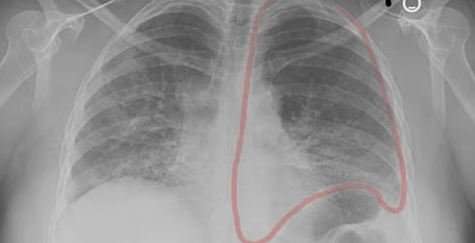

- 손톱 끝이 둥글게 부풀어 오르는 곤봉지

✔ 흉부 CT에서 이상 소견이 나온 경우